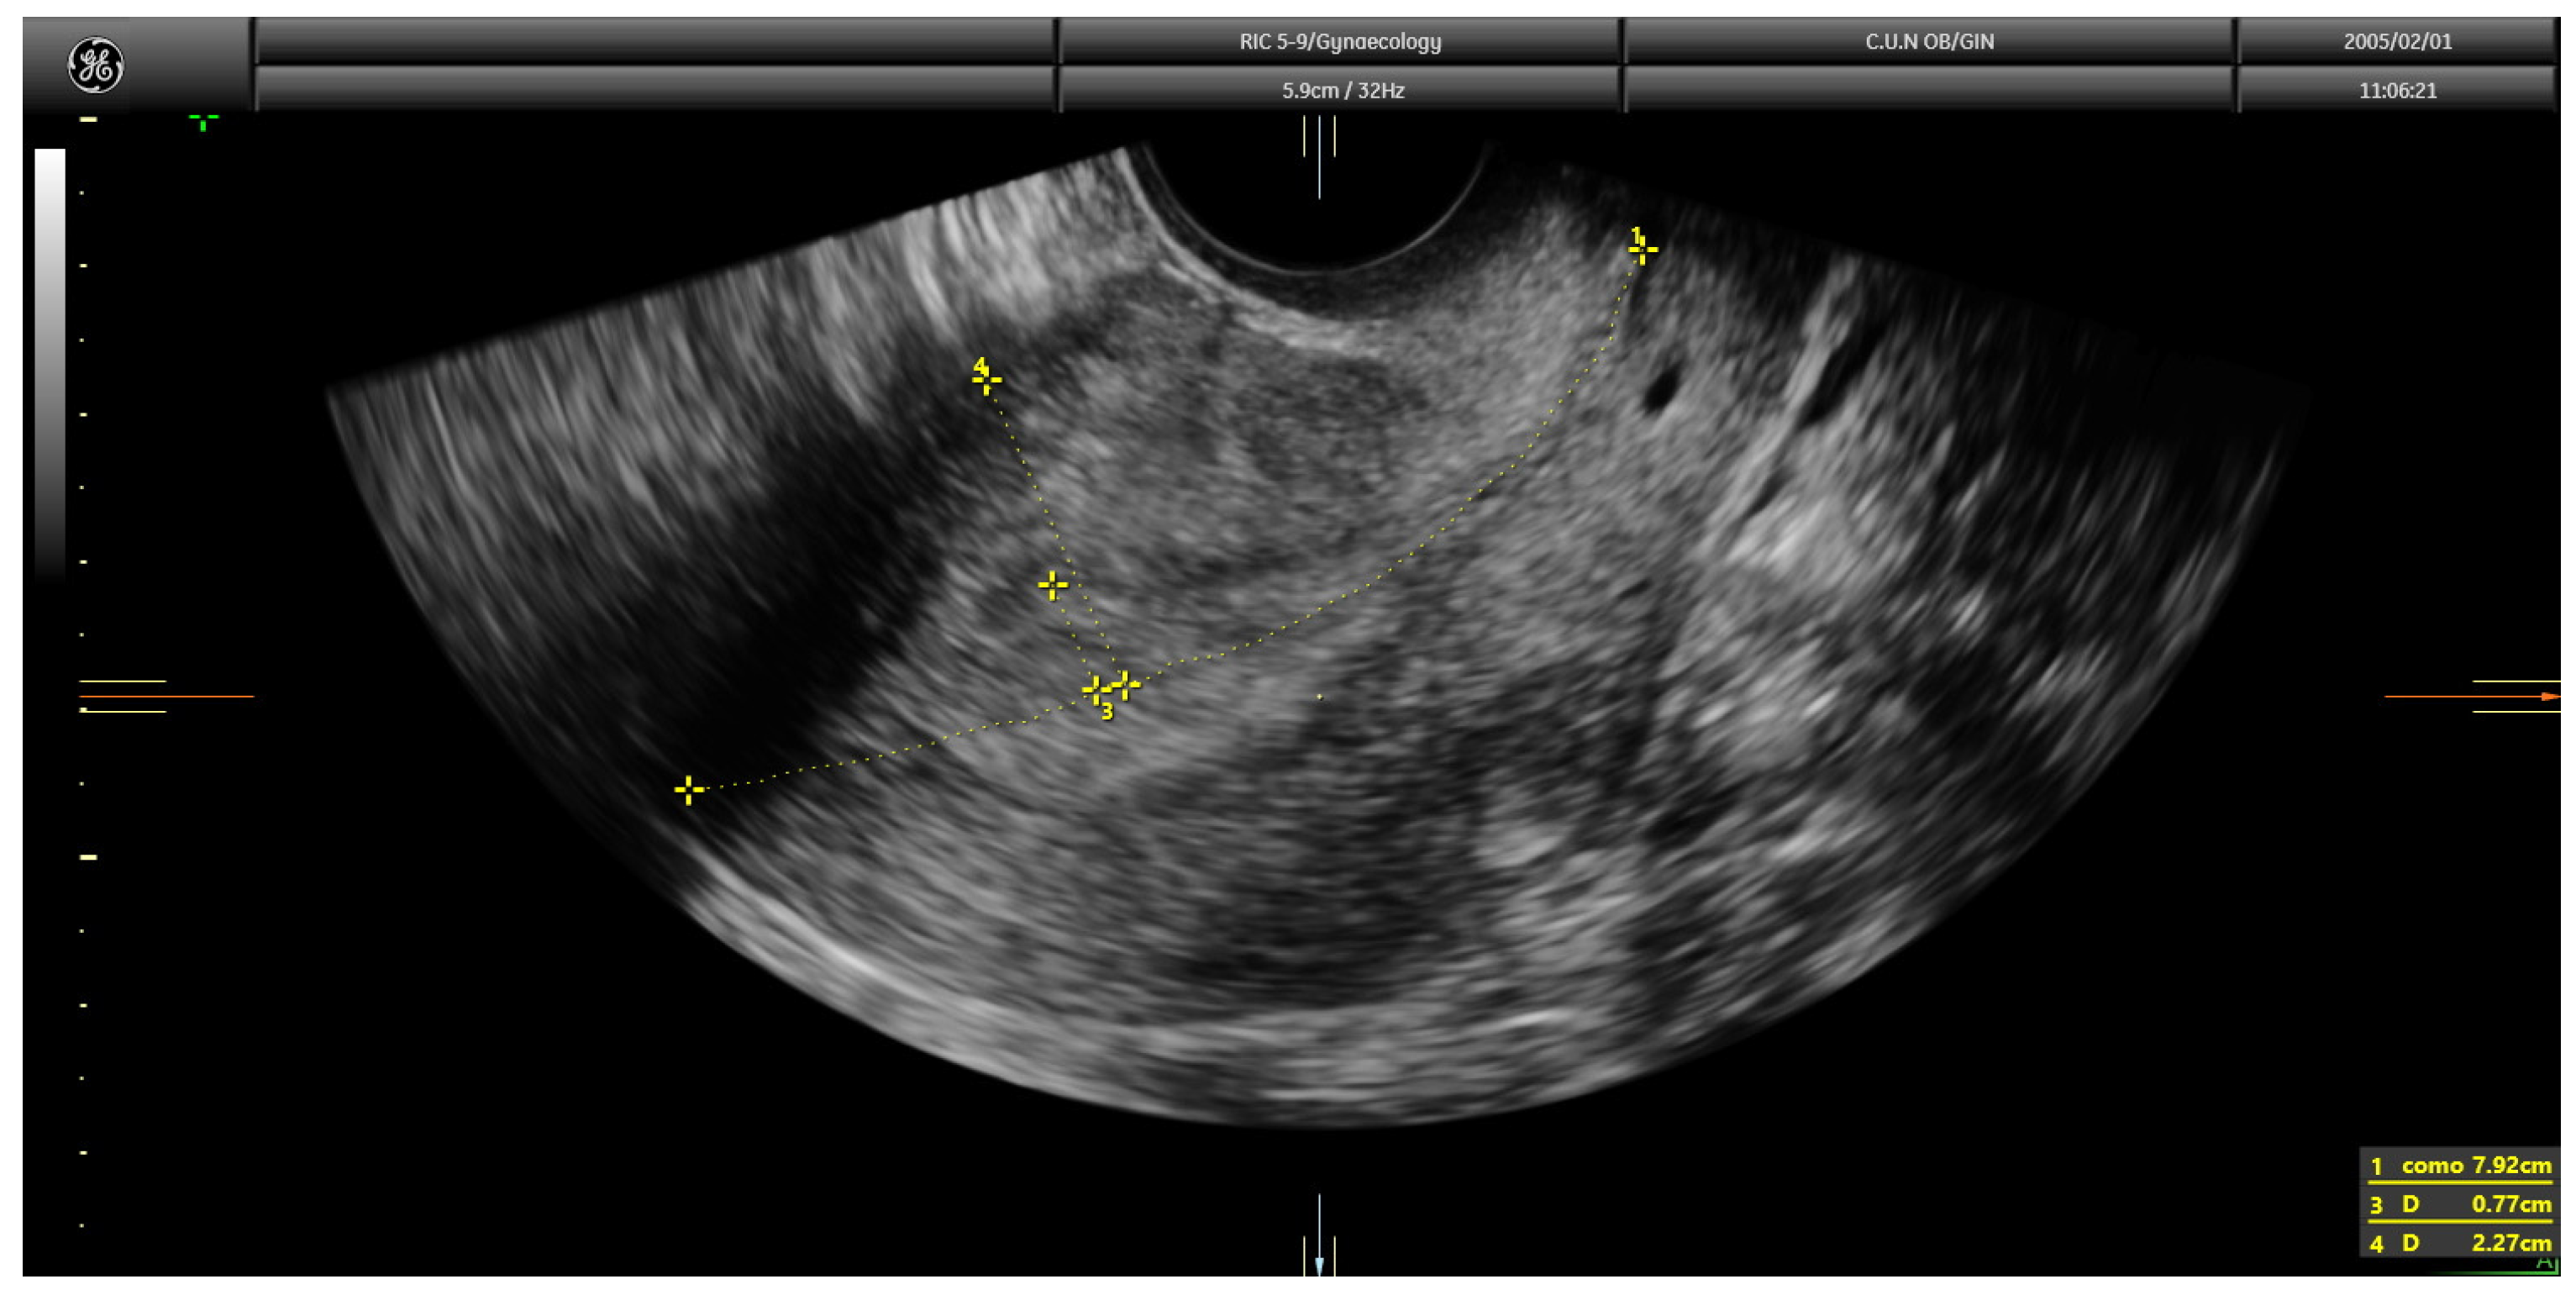

Obstetrical and Gynecologic Sonography and Transvaginal Sonography What Does A Shadow On The Womb Mean Enlarged uterus symptoms can include general discomfort and constipation, or the need to pee. if an ultrasound finds a hypoechoic mass, you may have wondered what that means. a hypoechoic mass. This condition occurs when the membranes or the sac that holds the fetus in the. sonography of the pelvis is the first resort and primary evaluation technique. What Does A Shadow On The Womb Mean.

What Does a Super Active Baby in Womb Mean? TQS Magazine What Does A Shadow On The Womb Mean Is an ultrasound term often seen behind calcification and some solid masses as a result of sound. ultrasound should be the diagnostic method of choice because you can actually “palpate” the uterus during the study and define a. sonography of the pelvis is the first resort and primary evaluation technique for any suspected pelvic pathology after clinical examination.. What Does A Shadow On The Womb Mean.